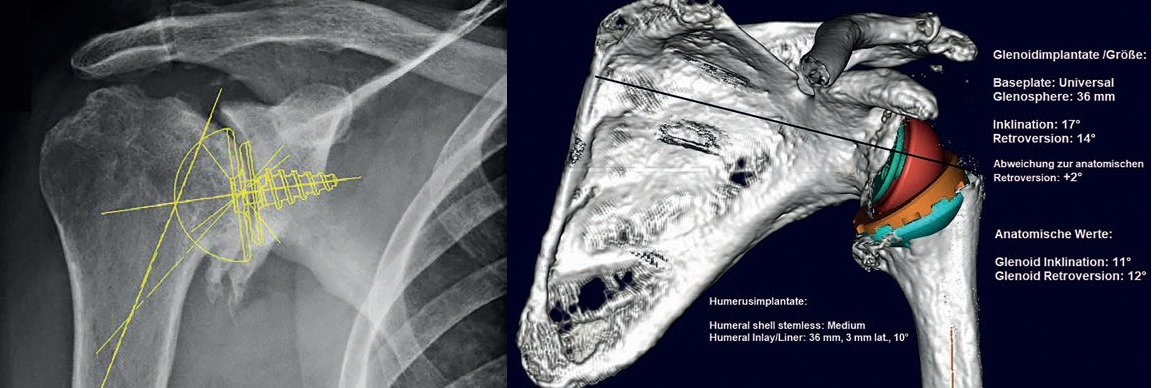

Früher hatte ich zunächst eher die Prothesenausrichtung geplant, mit den immer weiter verbesserten Planungssoftware-

Paketen und der Verfügbarkeit der digitalen Prothesenschablonen auch im Schulterbereich sind auch die Implantatgrößen

nun exakt planbar. Das reduziert den Aufwand mit verschiedenen Trials die Prothesengrößen zeitauwendig

intraoperativ zu bestimmen, spart Zeit und ist demnach hoch effektiv und effizient.

Meine Patienten bekommen von mir schon bereits seit ungefähr drei Jahren eine individuelle Planung vorgelegt und

unmittelbar nach der Operation mehrere, der Planung entsprechende, post-operative Röntgendurchleuchtungsbilder,

auf denen sie sehen können, dass die erfolgte Operation mit der erreichten Prothesenposition der Planung entspricht,

vor allem hinsichtlich Positionierung und bei 95% der Fälle auch hinsichtlich der Implantatgröße. Das gibt den Patienten

eine ernorme Sicherheit. Schließlich will jeder Patient bei der Visite nach der OP wissen „wie es gelaufen ist“. Wenn man

dann als Operateur sagen kann „alles nach Plan komplikationslos verlaufen, am Ende der Operation habe ich Ihr Gelenk

in allen wichtigen Stellungen getestet, es ist stabil und bewegt sich harmonisch“, und dies auch noch durch Bilder und

Dokumente belegen kann, gibt das den Patienten Vertrauen und Zufriedenheit.

Gerade das 3D-reponierte Gelenk, insbesondere bei der inversen Schulter TEP, mit sichtbarer implantierter Prothese

und Betrachtungsmöglichkeit aus jedem Blickwinkel im Raum, ist für mich derzeit noch etwas spannendes Neues mit

vielen noch möglichen Variablen. Derzeit versuche ich diese spielerisch herauszufinden, um die bisher bekannte optimale

Prothesenposition zu finden, anhand neuer Möglichkeiten zu überprüfen und zu validieren, idealerweise unter Berücksichtigung

von Weichteil-Spannungsverhältnissen durch Längenveränderungen. Anfangs habe ich für die gleichen